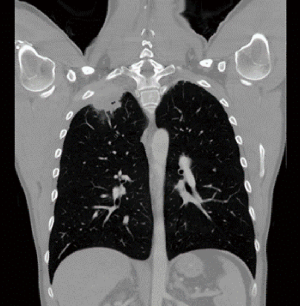

In lung cancer surgery, chest wall reconstruction may be required after chest wall resection performed due to direct invasion of the tumour into the chest wall. If the tumour is located in the lung apex (Figure 1) causing Pancoast syndrome, reconstruction is rarely indicated, however it may be necessary to prevent dropping of the shoulder and maintaining the shape of the chest wall close to normal. In these cases, the metal bars may be used to recreate the anatomically acceptable shape of the chest wall. StraTos bars (MedXpert, Germany) could be quite useful, because it is possible to bend them to the required shape and to secure them normally or in the invert position if required (Figure 2). The repair of the first rib is usually not possible and not usually performed.